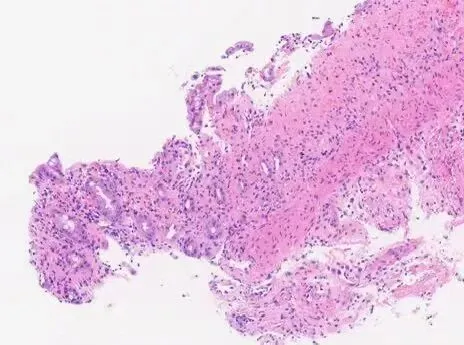

图2:缺血性结肠炎:黏膜表层损伤,固有层玻璃样变,隐窝萎缩,残余腺体排列密集

组织学形态

表层黏膜:显著损伤、脱落

隐窝:黏液减少、杯状细胞减少,“萎缩”的微小隐窝,残余腺体排列更紧密

固有层:玻璃样变(透明变),正常疏松结缔组织被致密嗜酸性基质替代,可见浆细胞、淋巴细胞、嗜酸性粒细胞浸润,伴固有层崩解